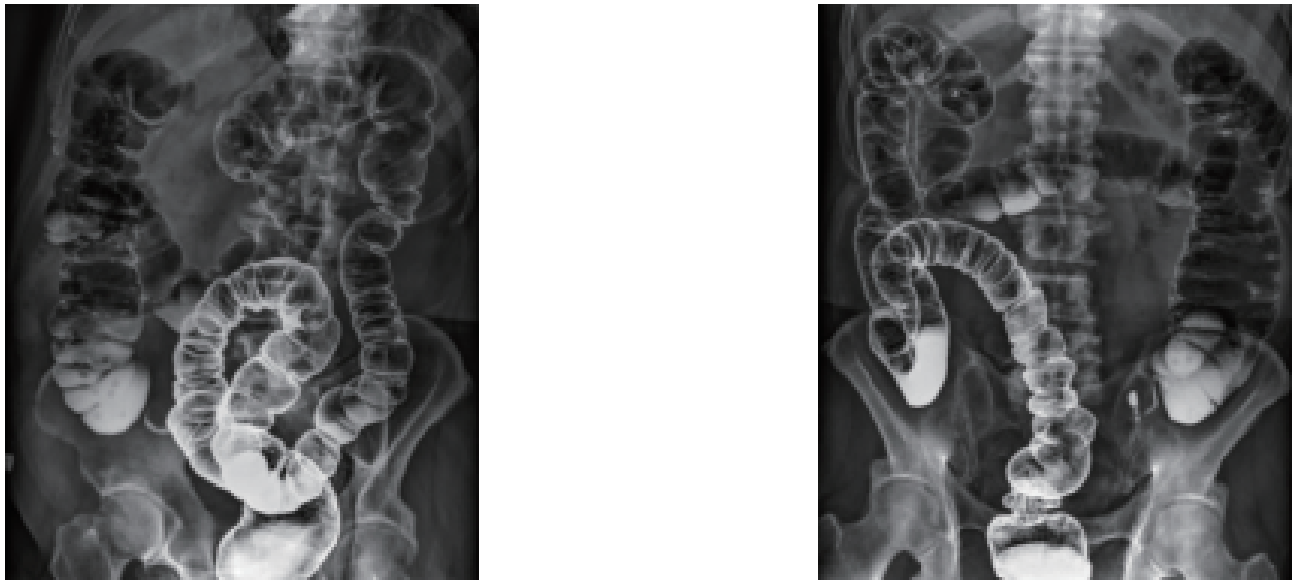

数字化透视:

为全身各部位透视、透视下定位、透视下穿刺及透视下数字点片摄影